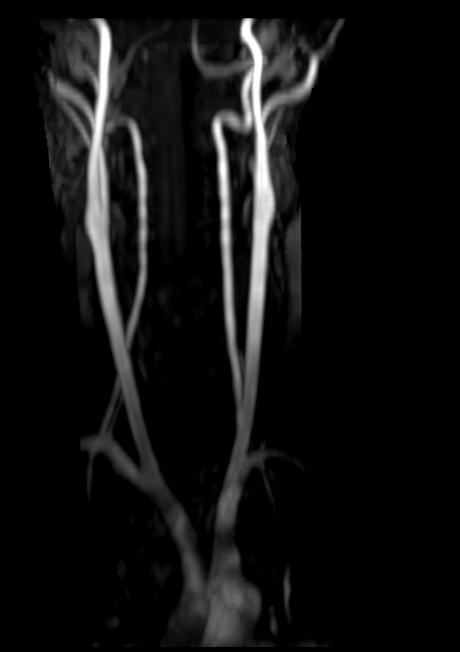

МР-артериография — неинвазивный безопасный метод исследования для диагностики патологии артериальной системы головного мозга. Магнитно-резонансная артериография позволяет получить трехмерное изображение сосудистой системы, кровоснабжающей центральную нервную систему, оценить анатомическое строение артерий головного мозга и функциональные особенности кровотока.

С помощью электромагнитных волн томограф послойно сканирует структуры исследуемого органа, затем посредством компьютерных программ преобразует полученные данные в трехмерное изображение. При этом на снимке видна только сосудистая система без окружающих тканей. Таким образом, сканирование в режиме ангиографии позволяет визуализировать артерии и вены головного мозга без контрастирования.